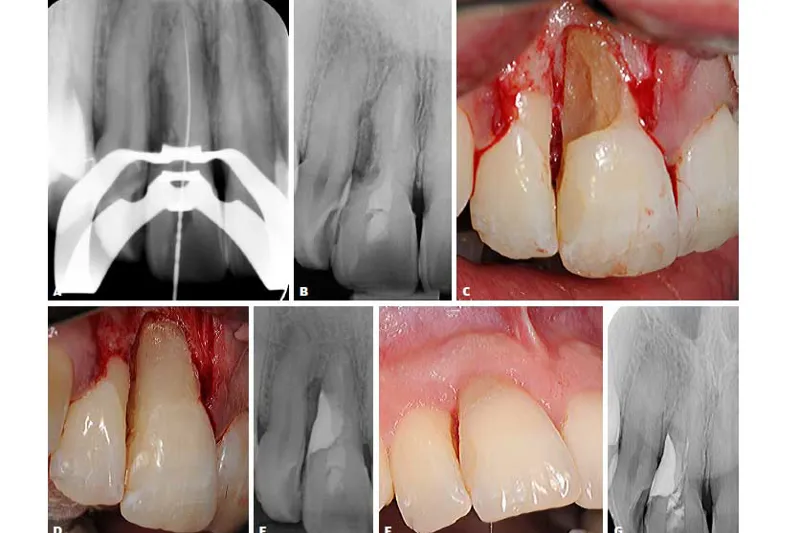

a491 fig. 3

I denne artikel beskrives eksempler på eksterne resorptionsforløb samt efterfølgende behandlinger, svarende til en tidlig reparationsrelateret overfladeresorption (ikke-infektion) samt senstadier af infektionsrelaterede inflammatoriske resorptioner på patienter med traumebelastede tandrødder. Den nekrotisk og bakterielt inficerede pulpa kan opretholde en resorption aktiv, og den eksterne resorption kan kompromitteres ved en parodontalt betinget infektion.

I det første patienttilfælde gennemgås et fejlagtigt behandlingsforløb samt vanskelighederne ved at opnå et klart diagnostisk grundlag omkring en tidlig reparationsrelateret overfladeresorption. I de efterfølgende to patienttilfælde redegøres for diagnostik, specifik behandling samt kontrol af den infektionsrelaterede resorptive proces med en infektiøs kontaminering marginalt.